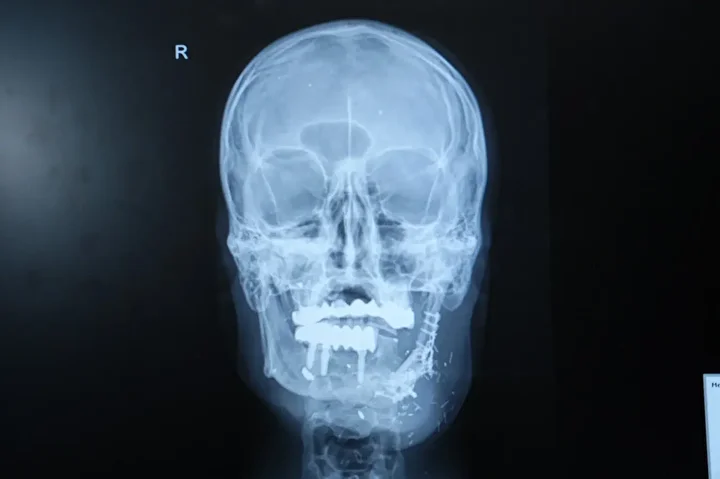

Hastanın durumunun oldukça komplike olduğunu dile getiren Doç. Dr. Özkan, “Hastamız ateşli silah yaralanması sonrası çenesinin yarısını kaybetmişti. Daha önce farklı merkezlerde ameliyat olmuş fakat nakiller başarısız olmuştu. Hem çene bütünlüğünü sağlamak hem de ileride implant yapılabilecek sağlam bir kemik dokusu oluşturmak gerekiyordu. Hastanın bacağından aldığımız kemiği mikrocerrahi yöntemle çeneye naklettik. Damarlara bağlantı yaptık, plaklarla sabitledik. Bu sayede hem fonksiyonel hem de estetik olarak başarılı bir sonuç elde ettik” dedi.

Doç. Dr. Özkan, bu tür vakalarda mikrocerrahinin önemine dikkat çekerek, “Kompozit doku eksikliklerinde vaskülerkemik transferi bize büyük avantaj sağlıyor. Hastamız şu an kendi beslenmesini sağlayabiliyor. Önümüzdeki süreçte kemik iyileşmesini tamamladıktan sonra diş implantları yerleştireceğiz ve hastamız çok daha rahat beslenebilecek” ifadelerini kullandı.